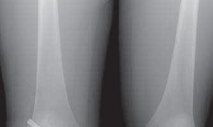

3. Routine radiographs, including weight-bearing anteroposterior and lateral views as well as patellar views, should be performed. In the revision setting, these images allow for critical assesment of previous tunnel placement and assesment for possible bone loss at previous tunnels, which may require further evaluation and treatment.

1. Metallic fixation devices make previous tunnel placement easy to identify, but bioabsorbable screws and other types of fixation also can be evaluated for tunnel placement on these images (

FIG 1

).

FIG 1 • A,B. Anterior cruciate ligament (ACL) reconstruction performed with an EndoButton (Smith & Nephew, Andover, MA) on the femur and staple fixation of the graft on the tibia. C,D. Anterior placement of the femoral tunnel in this primary ACL reconstruction performed with a two-incision technique. A B C

D